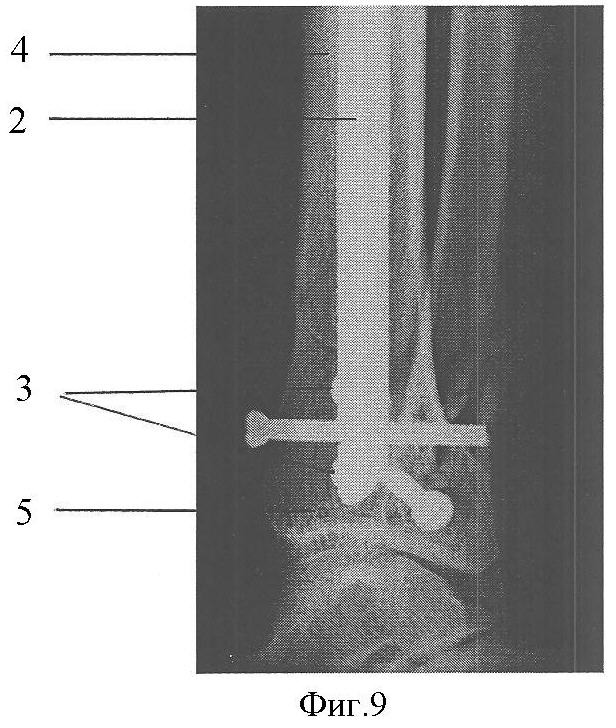

Фиг.9. Постоперационная рентгенограмма в боковой проекции.

Клинический пример: Пациентка А., 43 лет. Диагноз: Закрытый перелом дистальных метафизов обеих костей правой голени (фиг.4, 5). Произведена операция (фиг.8, 9), при этом после внедрения стержня 2 интрамедуллярно под контролем электронно-оптического преобразователя проведены репозиционно-блокирующие винты 3 через костные отломки 4, 5 и резьбовые отверстия 1 в стержне 2, при установке винтов 3 (фиг.3, 6, 7) достигнута компрессия отломков 4, 5 с устранением остаточных их смещений за счет притягивания отломков 4, 5 к стержню 2 головками винтов 3 и достигнута окончательная репозиция и полиаксиальная жесткая стабилизация отломков 4, 5, исключающих возможность смещений отломков 4,5 после установки металлоконструкции и в послеоперационном периоде. Винты 3 выполнили как репонирующую, так и блокирующую роль. Полная нагрузка на ногу после операции (фиг.10). Срок нетрудоспособности 4 недели.